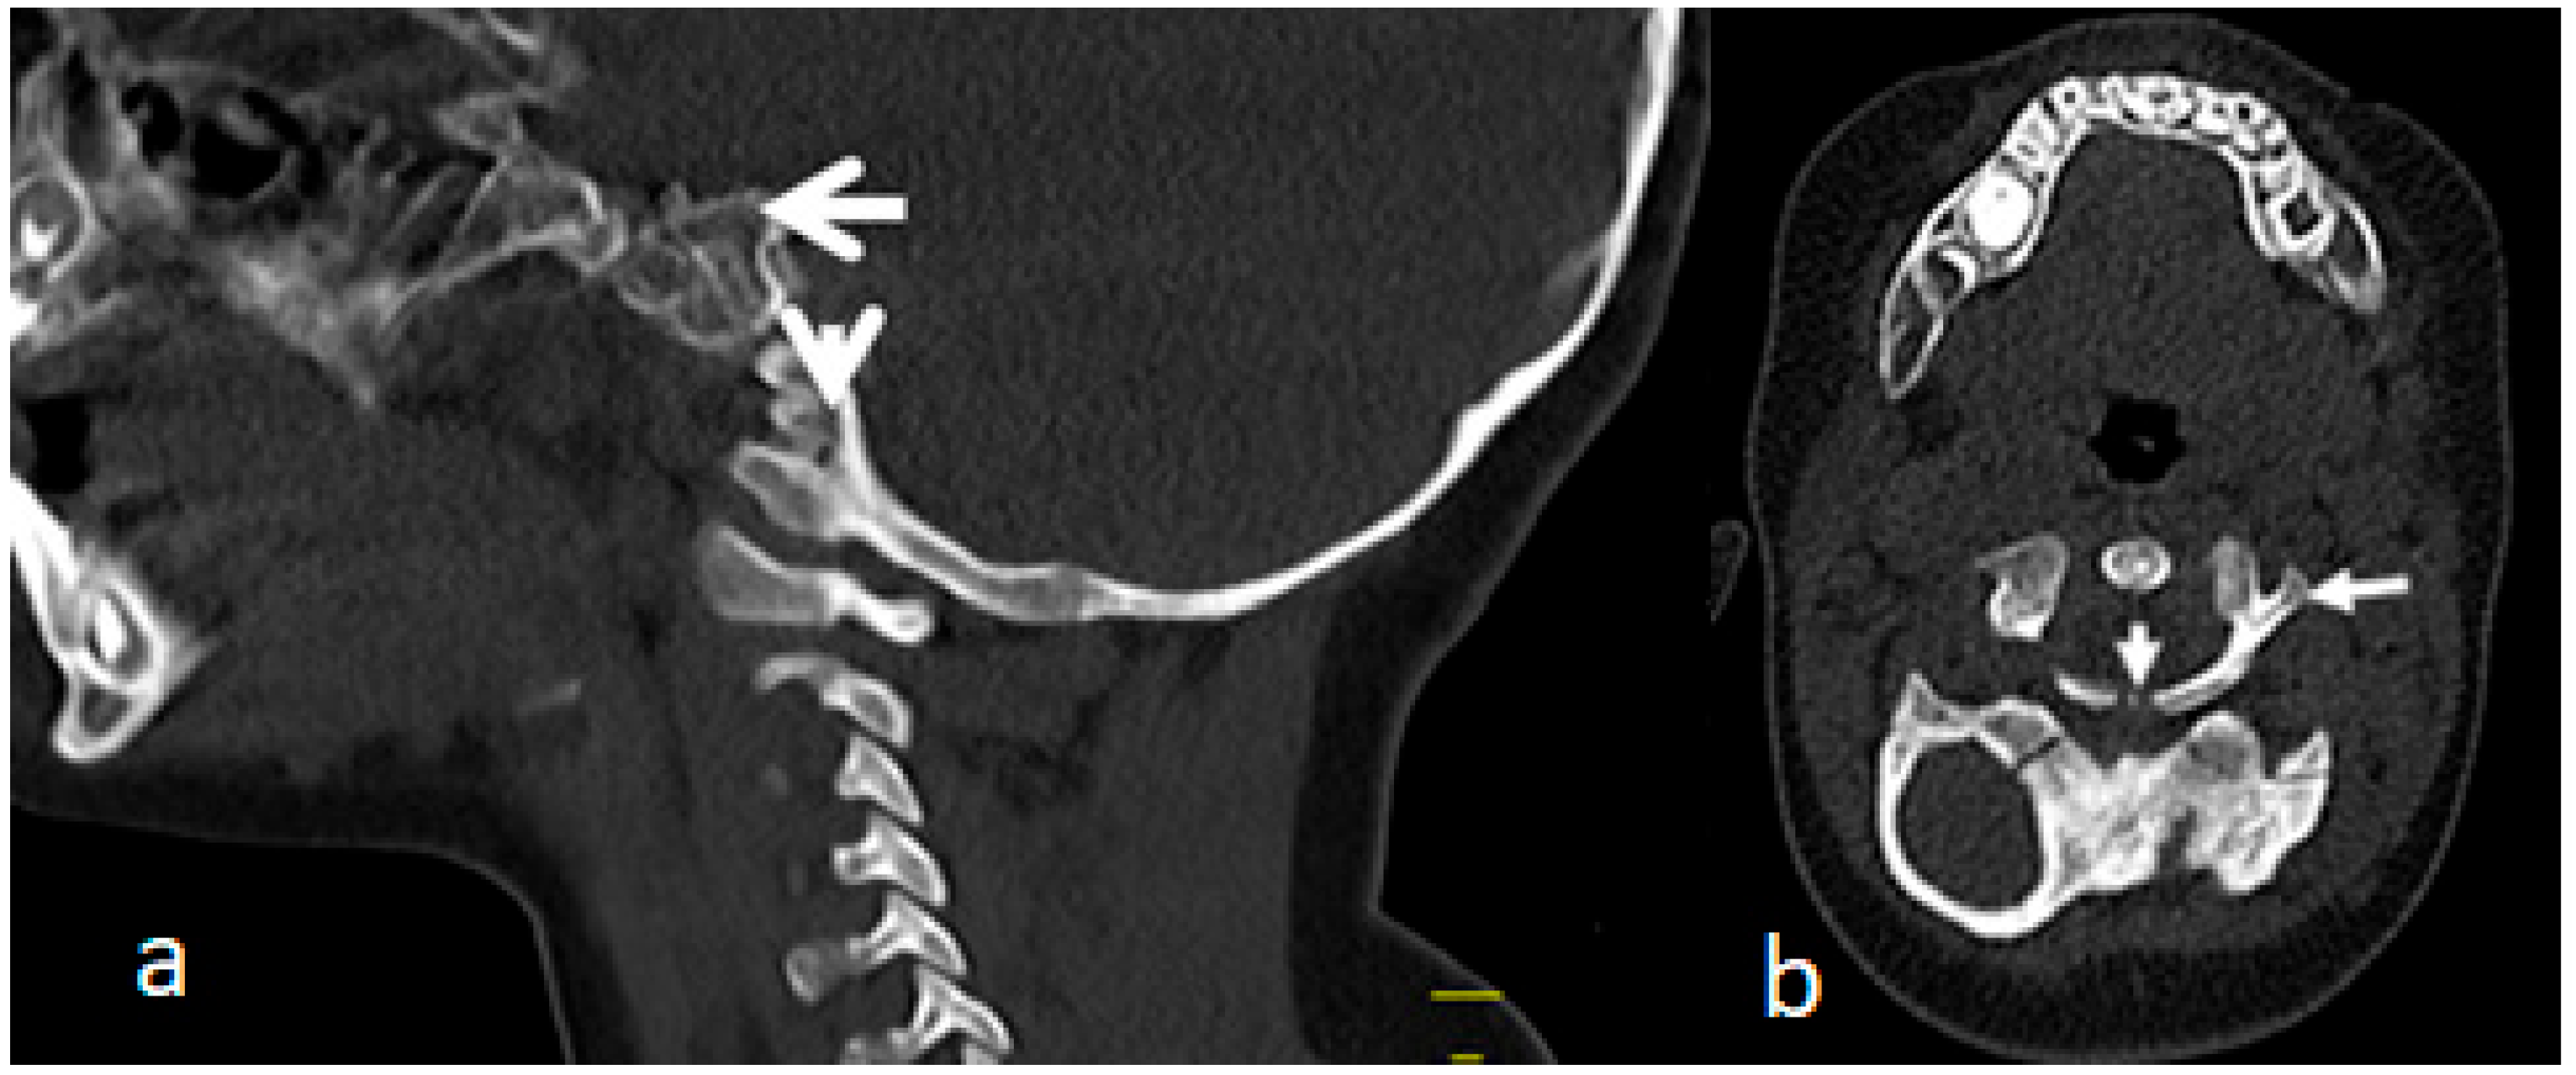

3.2. Congenital Tetraplegia in a Child with Larsen Syndrome

Congenital tetraplegia has been never described in children with Larsen syndrome. The overall clinical criteria of the lethal type of Larsen syndrome, which is characterized by immediate death after birth, is not consistent with our current child. However, no CT scan studies for the craniocervical junctions have been described in the lethal type of Larsen syndrome.

A 3D-reformatted sagittal CT scan of the cranium shows a six-month-old-child who was born with congenital tetraplegia. Maldevelopment of the anterior ring of the atlas C1, which has been displaced along the superior surface of the clivus, is also evident. Also, the (odontoid process is hypoplastic and dislocated and 9s located between the maldeveloped anterior rings) (arrow head). Fusion of the fragmented anterior and posterior rings of C1 and fusion of these fragments effect the development of a bifurcation-like structure (Figure 4a). An axial 3D-reformatted CT scan shows congenital maldevelopment of the anterior arch of the atlas and fusion of the remnants of anterior ring with the lateral mass of C1 (forming a Y-shaped deformity) (arrow head). The posterior ring of C1 is hypoplastic, resembling a Jefferson fracture (arrow head) (Figure 4b).

Figure 4.

(a,b). A 3D-reformatted sagittal CT scan of the cranium in a six-month-old child with Larsen syndrome who was born with congenital tetraplagia. Note the maldevelopment of the anterior ring of the atlas C1, which has been displaced along the superior surface of the clivus. Also, the odontoid process is hypoplastic and dislocated and displaced between the defectively developed anterior rings (arrow head). Fusion of the fragmented anterior and posterior rings of C1 and fusion of these fragments causing effectively the development of a Y-shaped deformity (a). Axial 3D-reformatted CT scan showing congenital maldevelopment of the anterior arch of the atlas and fusion of the remnants of the anterior ring with the lateral mass of C1 (forming a Y-shaped bone deformity) (arrow head). The posterior ring of C1 is hypoplastic resembling a Jefferson fracture (arrow head) (b).